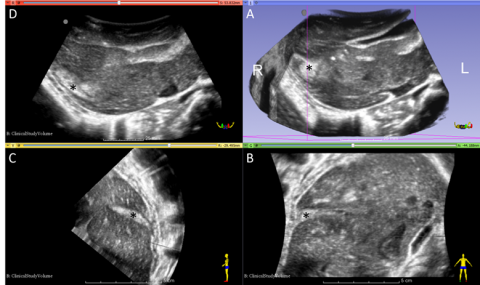

How a $10 Microchip Turns 2-D Ultrasound Machines to 3-D Imaging Devices

Dr. Josh Broder, Division of Emergency Medicine, demonstrates the low-cost, point-of-care ultrasound device

Duke Emergency Medicine Team Selected as Finalist for GE/Emergency Medicine Foundation Challenge

A team from the Division of Emergency Medicine has been selected as one of four finalists for the GE/Emergency Medicine Foundation Challenge for their work in 3D ultrasound (US) of traumatic shock.